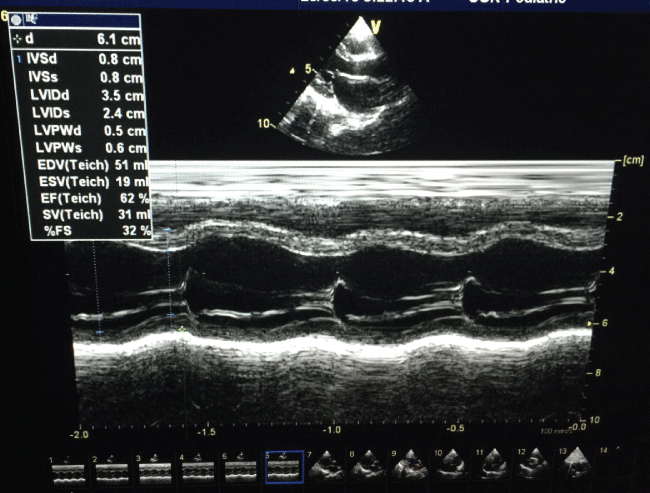

ECG showed low voltage. Besides, an echocardiogram (ECHO) noted severe ventricular dysfunction with FS 15%, and poor contractility (Figure 1a), which were improved on follow up.

At 1-month follow-up, the patient remained asymptomatic and with ECHO reflected an improved cardiac function, FS 27%. Six months later, repeated ECHO showed improved myocarditis with FS 34% (Figure 1b), he was advised to continue on having captopril and furosemide.